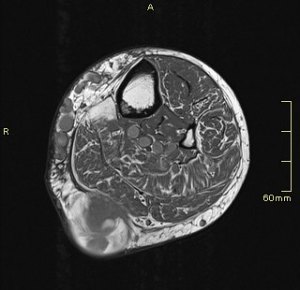

En el corte axial de las imágenes 3 y 4 puedes ver la anatomía radiológica implicada. La relación es perfecta, y completamente explicativa de la situación resulta mediante el tratamiento quirúrgico. En ella la Arteria iliaca derecha para justo por encima de la Vena iliaca Izquierda con la capacidad de poder comprimirla.